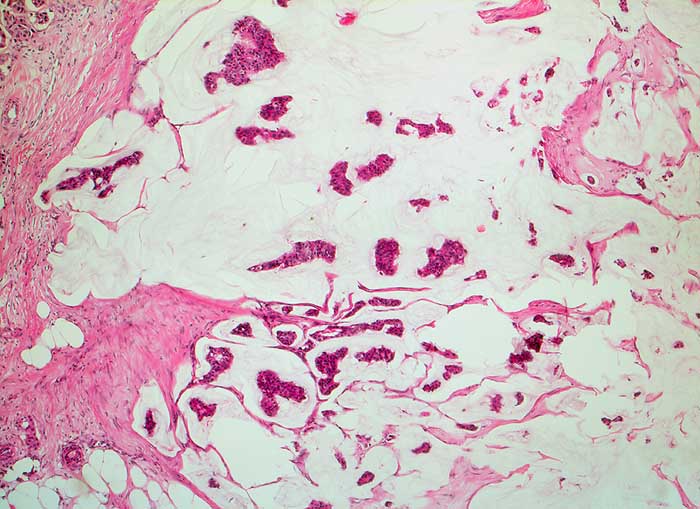

PathoPic ID 5692 - muzinöses Mammakarzinom

muzinöses Mammakarzinom

maligner Tumor

Mamma

Schleimseen mit inselförmigen Tumorzellverbänden umgeben von Bindegewebssepten.

Karzinomrezidiv parasternal links nach Mastektomie

Zytologische Diagnose: muzinöses Karzinom

Histologie

50